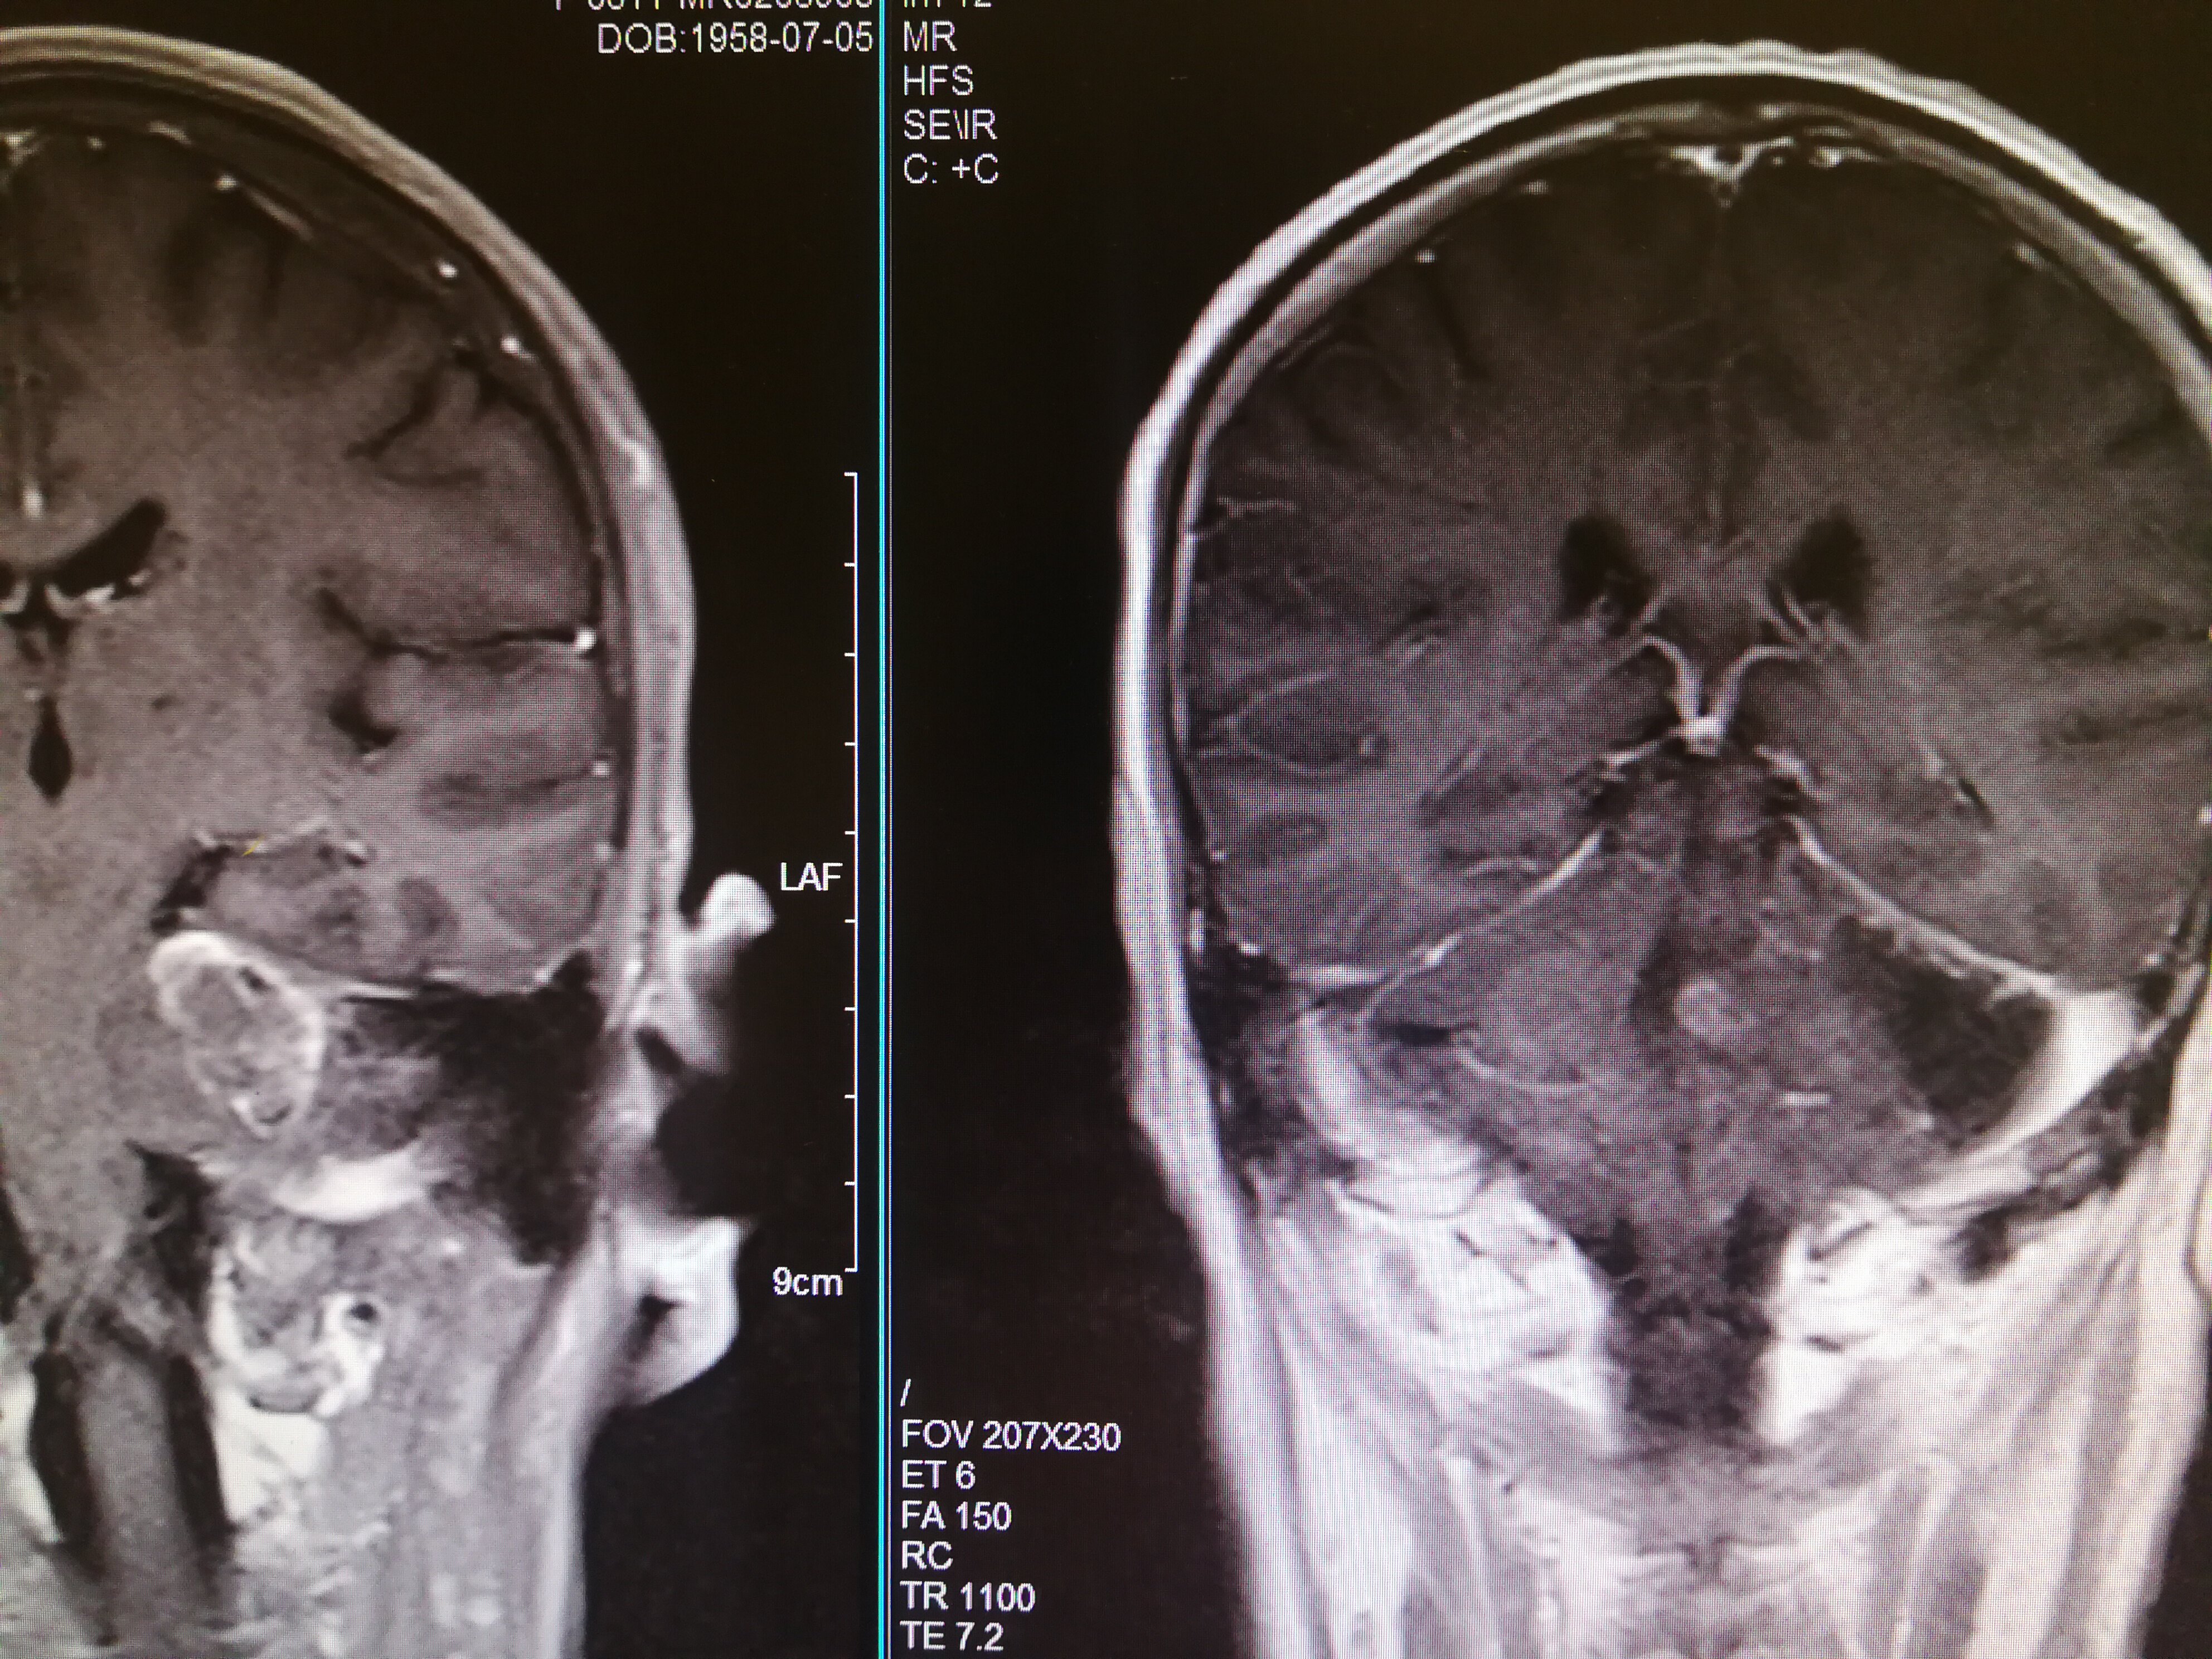

手术治疗听神经瘤是最主要的治疗方式,目前听神经瘤的手术已经非常成熟,只要没有明显的手术禁忌症首先应考虑手术治疗,并要求在电生理监测条件下完成手术,这样可以最大限度地保护面神经功能。以下是几例我们做的听神经鞘瘤手术前后核磁共振片子对照,除手术后听力不能恢复外,没有面瘫,脸部麻木,吞咽困难等颅神经症状,也无其他较明显的手术并发症发生。